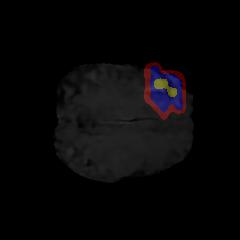

Brain tumor segmentation. Segmenting tumors in brain is challenging due to the high variance in appearance and shape of the tumors [28]. We use a subset of the 2017 Brain Tumour Image Segmentation (BraTS) dataset [29, 26]. It contains multi-parametric 3D MRI scans. The segmentation masks include (possibly overlapping) three classes of tumor. The 3D scans are split into 2D image slices, and only images that contain at least one tumor class are retained. Figure 7 shows three MSGNet generated samples as well as the corresponding masks. Since MSGNet adheres to the underlying relationships between various classes, we see that the generated images and the masks for different tumor classes are in line with the images and masks from the training set. In general, MSGNet rarely generated erroneous samples; we found roughly one sample per 3000 generations that could be rejected. Similar to the malaria experiment, we observed an improvement of 3.1% () in -score on the validation set.

A subset of the BrATS dataset was used. We used the images accompanied by segmentation layouts from the FLAIR and T1Gd modes. The segmentation layouts showed the sub-regions for three different classes: GD-enhancing tumor, the peritumoral edema, and the necrotic and non-enhancing tumor core. The brain and the background were treated as an additional class. We refer to [32] for further details. For the two modes, the background has been modelled using two different classes. We only considered half of the 155 slices, i.e., we took only the even-numbered slices and out of those we discarded the slices that did not include one of the previously mentioned tumor-classes in order to create a more balanced dataset. This resulted in 20,000 images that were further augmented with 6,000 MSGNet generated images. Example generations of the masks as well as the images are shown in Figure 12.